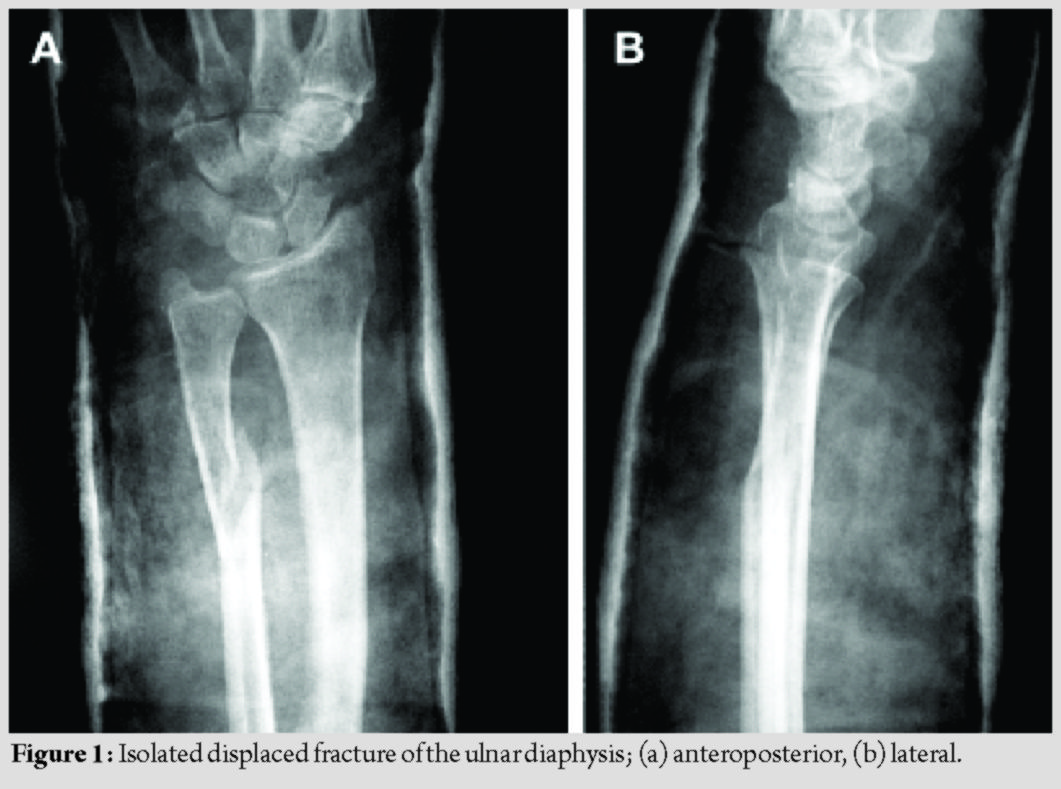

Isolated ulnar diaphyseal fractures are relatively rare [1]; however, they have a high complication rate [1, 2]. When located in the distal two-thirds of the ulna, with <50% displacement and less than 10 degrees angulation, they may be treated non-operatively [3]. All other types are considered unstable and are treated operatively with internal fixation [1, 2, 3]. Although absorbable implants have been used as fixation devices, their use for treating isolated ulnar diaphyseal fractures in adults has not yet been studied [4, 5, 6, 7, 8]. The aim of this study was to assess the outcomes of fixation with third-generation Inion OTPSTM absorbable implants consisting of L-lactide, D, L-lactide, and trimethylene carbonate in a series of patients with isolated ulnar fractures. The mechanical stability of the implants, their complications, including late-presenting foreign body reactions, and the final clinical result were evaluated. This case series study was approved by the institution’s ethics committee (74/16-4-2005). From April 2005 to December 2006, three patients with displaced, isolated ulnar diaphyseal fractures were enrolled (mean age 45 years old) (Fig. 1). Patients with complex fractures of both radius and ulna, osteoporosis, a history of other pathological or hereditary bone disorders that affect bone metabolism, and smokers were excluded from the study. All patients provided written informed consent. In January 2007, both the orthopaedic team and the ethics committee decided discontinuation of the study, due to early implant failure and no added benefit to the patients.

The patients’ demographics and comorbidities are shown in Table 1. All three patients reported pain and unexpected swelling few days after the operation and the implants’ failure was confirmed radiologically (Fig. 4).